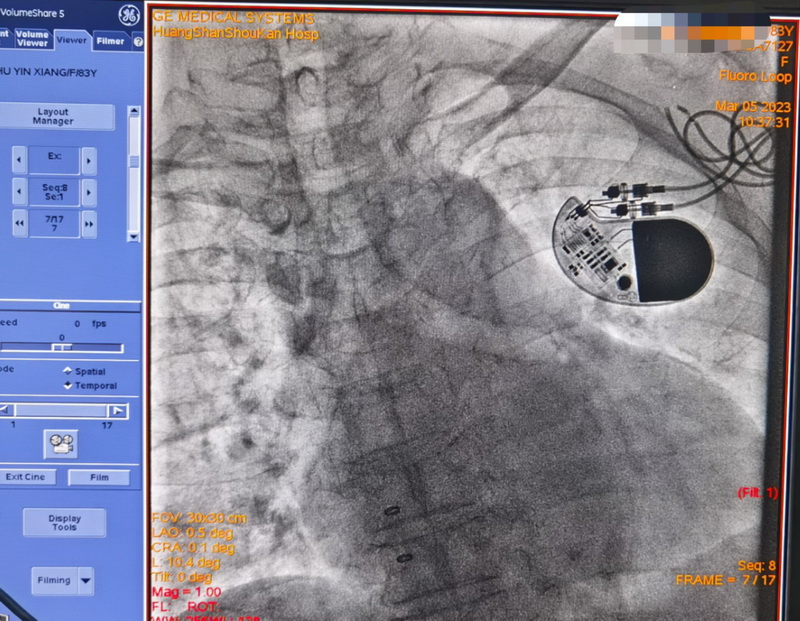

3月5日,外院专家与心内科团队历经2小时,按照预定的方案顺利拔除了起搏导线,攻克了整个医疗过程中最为困难的一步。

术后朱奶奶情况一直很稳定。经讨论后,为避免类似的问题再次发生,吴捷华主任决定为朱奶奶植入无导线起搏器。相较于传统心脏起搏器,无导线起搏器体积缩小了90%,且弥补了传统起搏器电极导线需要导线进行脉冲的缺点,将脉冲发生器和电极合为一体,未来不会产生囊袋破损感染的风险。

半个多月后,随着双腔无导线起搏器成功植入在朱奶奶体内,囊袋感染的第二次心脏危机被彻底解除。朱奶奶的心脏又继续忠诚地履行起它的职责,继续有规律地跳动。